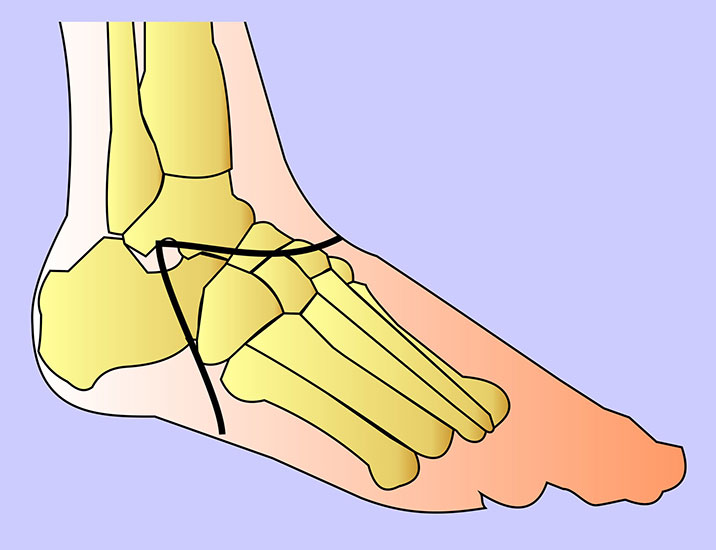

Schema der Amputationsniveaus am Fuß von der Seite.

Grün: empfohlene Amputationslinien.

Rot: nicht empfohlene Amputationslinie.

Abbildung 1

Die Amputationslinien am Fuß, die sich uns bewährt haben, sind in der Abb. 1 schematisch dargestellt.